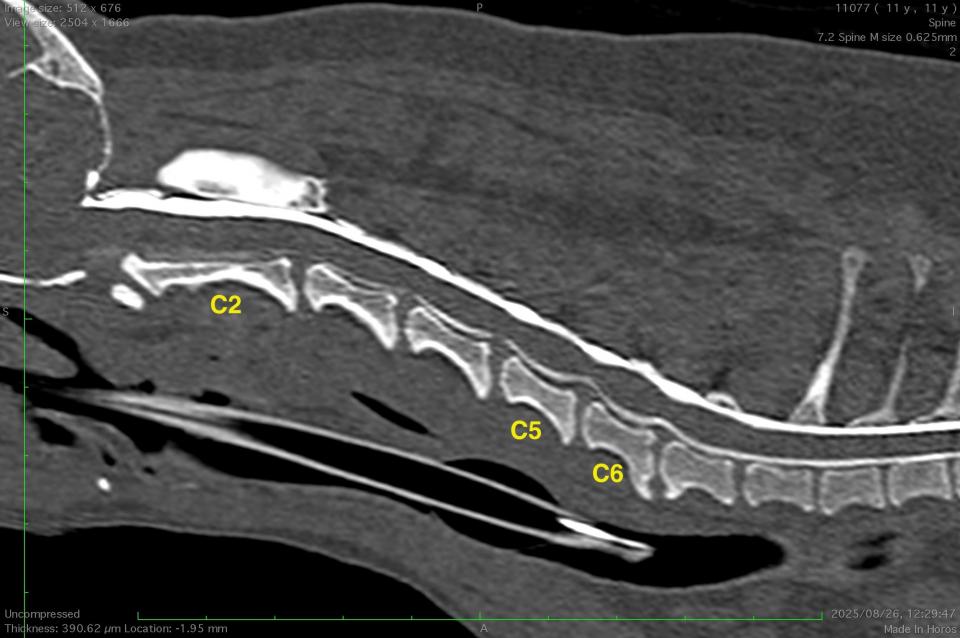

C2-3-4-5-6椎間において多発性椎間板ヘルニアが認められました。

責任病変の特定と椎間板関連動的圧迫の検出のための脊髄造影検査/脊髄造影ダイナミック検査を実施したところ、C5-6椎間において伸展時に圧迫の程度が悪化し、牽引時に軽減する脊髄動的圧迫所見が認められました。

本症例は脊髄造影検査および脊髄造影ダイナミック検査を実施することで、C5-6椎間の椎間板ヘルニアおよび脊椎不安定症と診断することができました。